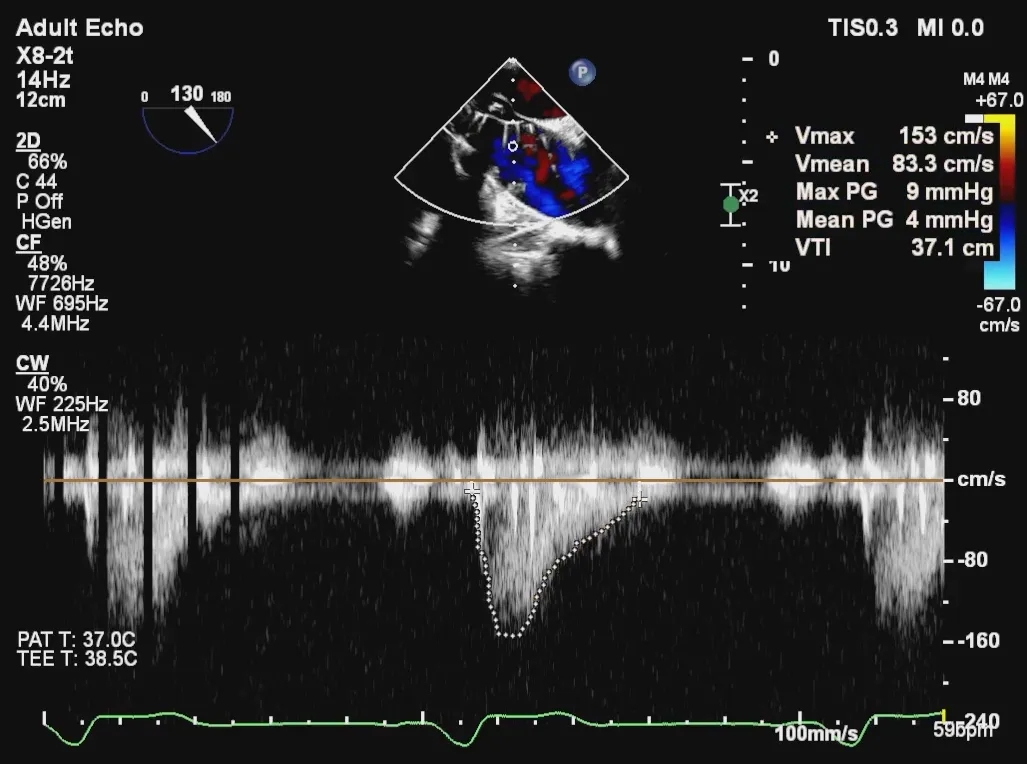

术后超声评估,瓣膜位置深度满意,形态可,微量瓣周漏,最大血流速度1.53m/s,平均跨瓣压差4mmHg。

术后超声提示人工瓣膜功能良好,平均跨瓣压差仅4mmHg,血流动力学改善显著。值得一提的是,术中选用的Evolut PRO瓣膜系统凭借其可回收、可重新定位的设计特点,为术中调整释放位置提供了重要技术支持,确保了瓣膜的稳定锚定与功能良好。此例手术的成功,充分展现了全超声引导TAVR在治疗二叶式主动脉瓣狭窄方面的可行性与安全性,为华中地区开展绿色介入技术积累了宝贵经验。